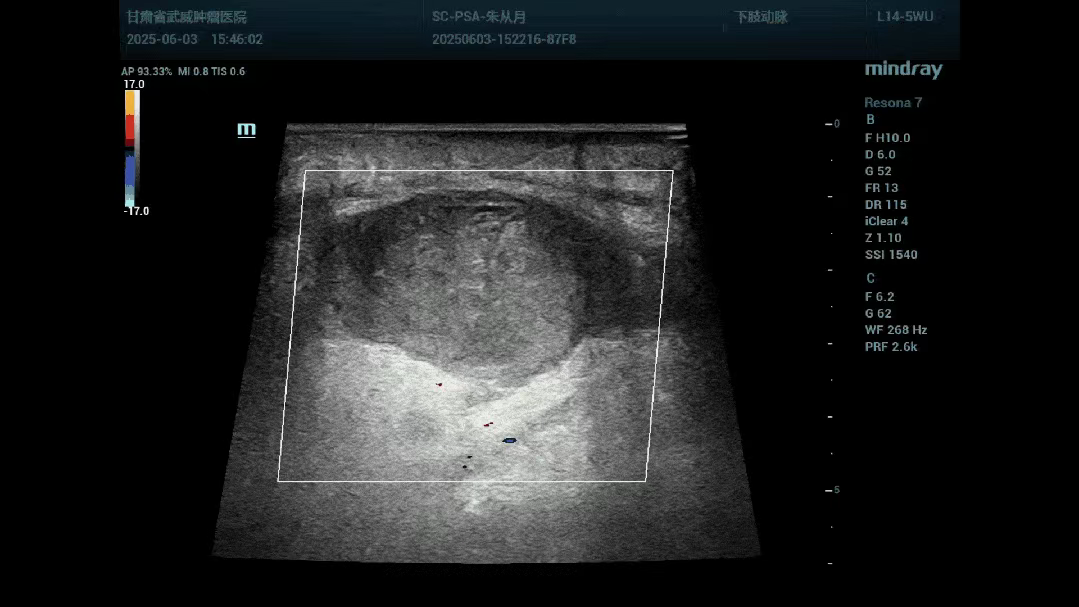

患者朱大妈因进行介入手术后,于右侧股动脉穿刺点形成一假性动脉瘤,大小约5cm左右,加压包扎未能取得良好效果。介入手术很成功,但是穿刺点形成的假性动脉瘤让患者疼痛不适,且右侧腹股沟区皮下形成斑片状青紫区域,进一步增加了朱大妈的心理压力。主管医师通过各种渠道多方咨询,联系到超声医学科寻求帮助。超声医学科通过了解患者病情,检查假性动脉瘤位于右侧股动脉前方,瘤腔大小约48x32mm,与股动脉交通口宽约2mm,内部血流呈旋涡状,彩色血流呈现“太极征”(如图1、2)。与临床医师共同讨论制定治疗方案:在超声实时引导下,向假性动脉瘤内精准注射凝血酶散,促进瘤体内血液凝固迅速形成血栓以堵塞瘤腔(如图3),从而达到治疗目的。超声医学科与主管医师精心做好术前准备,严格按设计流程顺利完成治疗,整个治疗过程约十分钟左右。术后1小时疼痛不适明显减轻,朱大妈十分感谢主管医师为她解决病痛,高高兴兴出院回家了。这就是介入超声的魅力所在,实时精准、方便快捷、疗效肯定,整个治疗过程患者无明显不适,可迅速为临床医师解决棘手问题。

图三:假性动脉瘤治疗后